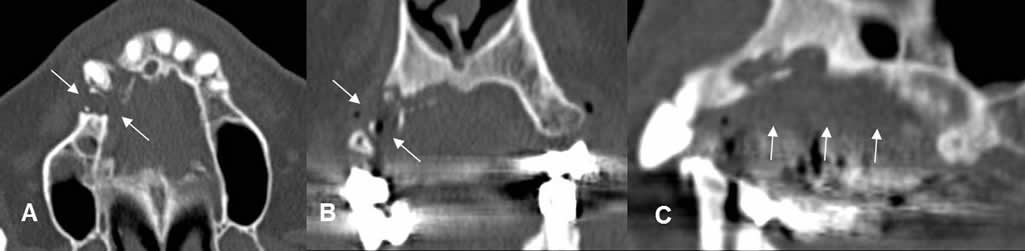

Fig 33 C. Infección del implante.

A: TAC axial, B: TAC reconstrucción coronal y C: TAC reconstrucción sagital. Infección del implante, el cual se ha caído. Hay gran lesión lítica que destruye el maxilar, por osteomielitis.